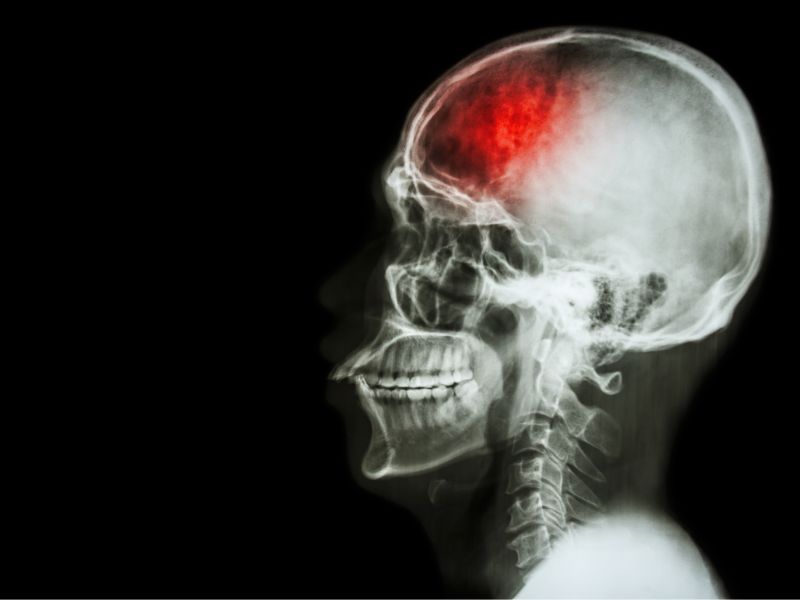

Đột quỵ – “sát thủ thầm lặng” có thể xảy ra với bất kỳ ai và đang có dấu hiệu trẻ hóa trong những năm gần đây. Cùng tìm hiểu về bệnh và có phát hiện sớm để điều trị kịp thời nhé.

Đột quỵ (tai biến mạch máu não) là nguyên nhân hàng đầu gây tử vong và tàn phế trên toàn thế giới. Chỉ trong vài phút ngắn ngủi, các sự sống có thể thay đổi hoàn toàn.

Nhiều người vẫn lầm tưởng đột quỵ chỉ xảy ra ở người cao tuổi. Thực tế, ngay cả người trẻ, đang ở đỉnh cao của sự nghiệp và cảm thấy khỏe mạnh vẫn có thể bị đột quỵ bất ngờ. Theo một số thống kê, 80% ca đột quỵ liên quan đến các rối loạn chuyển hóa, nhưng phần lớn bệnh nhân lại không hề biết mình đang mắc bệnh.